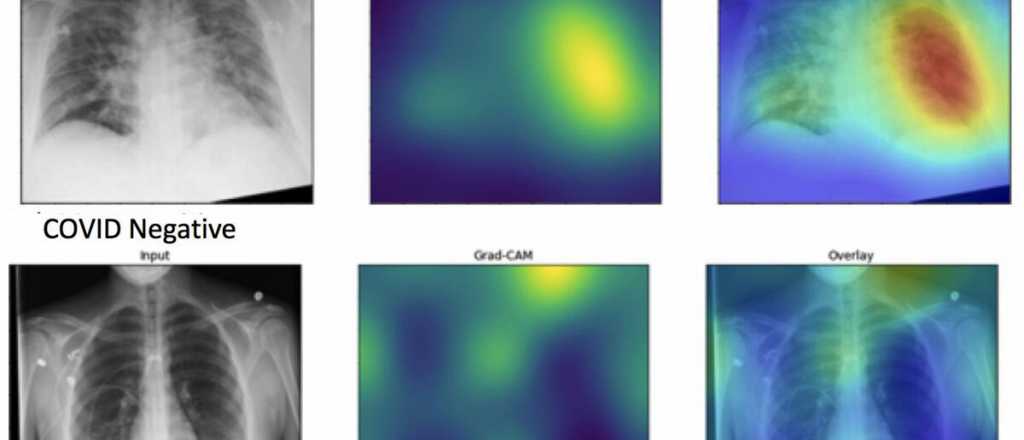

Científicos de la Universidad Nortwestern de EE.UU. desarrollaron una plataforma con la cual a través de una radiografía y con Inteligencia Artificial pueden detectar pacientes con coronavirus, por cómo se ven sus pulmones.

Los pulmones con Covid-19 se ven así con Inteligencia Artificial

Entre los últimos estudios publicados, científicos de la Universidad Nortwestern, en Estados Unidos, desarrolló una aplicación con Inteligencia Artificial con la cual a través de rayos X, una simple radiografía, se puede advertir en los pulmones lo que genera el Covid-19 en los pacientes.

Crearon una plataforma con cuyo algoritmo es posible diagnosticar con precisión y rapidez si una persona puede tener el coronavirus o no.

Se llama DeepCOVID-XR, y su algoritmo de aprendizaje automático superó a un equipo de radiólogos toráxicos especializados. La máquina ubicó el COVID-19 diez veces más rápido que los expertos, y con una precisión del 1 al 6%.

Para muchos pacientes con covid-19, las radiografías de tórax muestran patrones similares. En lugar de pulmones limpios y sanos, sus pulmones se ven irregulares y confusos.